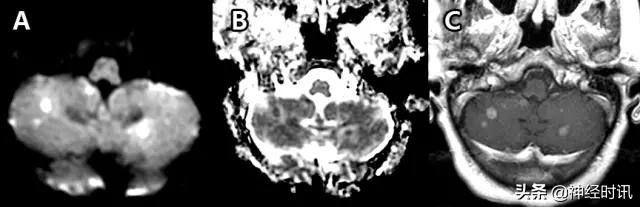

图24 一位51岁的女性小细胞肺癌患者,因每天早晨突然出现的恶心、呕吐而就诊。其小脑存在多发性弥散受限病灶(A:DWI,B:ADC),并伴有强化(C:T1WI增强扫描)。

转移性病变

大量细胞转移灶,尤其是小细胞肺癌,可以表现为因致密细胞聚集所致的弥散受限,且可能与急性或亚急性栓塞性卒中相混淆(图24)。前者的一些鉴别特征包括存在周边血管性水肿、周边强化和其它的脑实质外病变(如颅骨病变)。